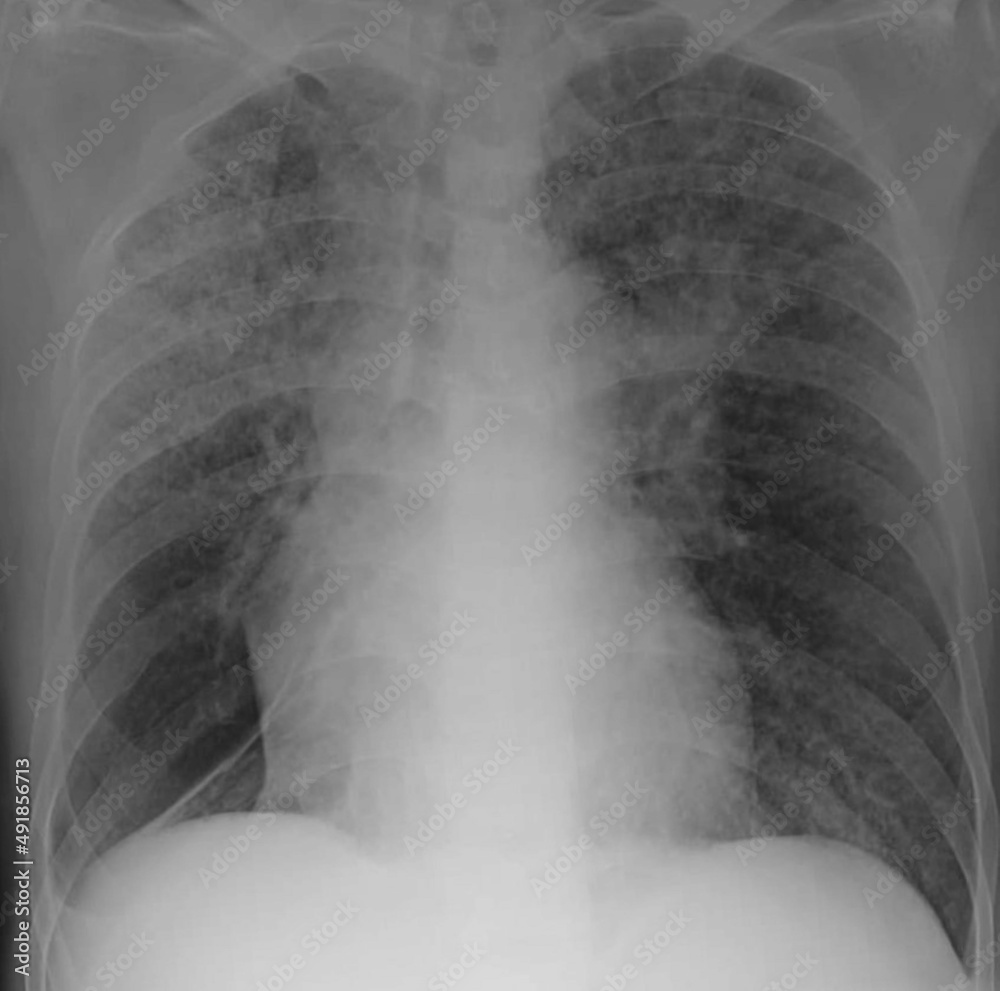

Chest XRay (November 23 th , 2017) showing a typical miliary pattern

chest xray image of miliary nodules Stock Photo Adobe Stock Miliary Chest X Ray Differential Diagnosis miliary nodules can be the manifestation of multiple diseases and the differential diagnosis is broad once. There are 3 major patterns of pulmonary opacity: Nodular—small (2 to 3 mm), medium, large, or masses (>3 cm) 3. Reticular—fine or coarse linear shadows. differential diagnosis of diffuse micronodular disease miliary nodules can be the manifestation of multiple diseases. miliary. Miliary Chest X Ray Differential Diagnosis.